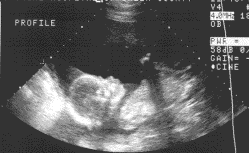

echo lever echotoestel

pre natale echo